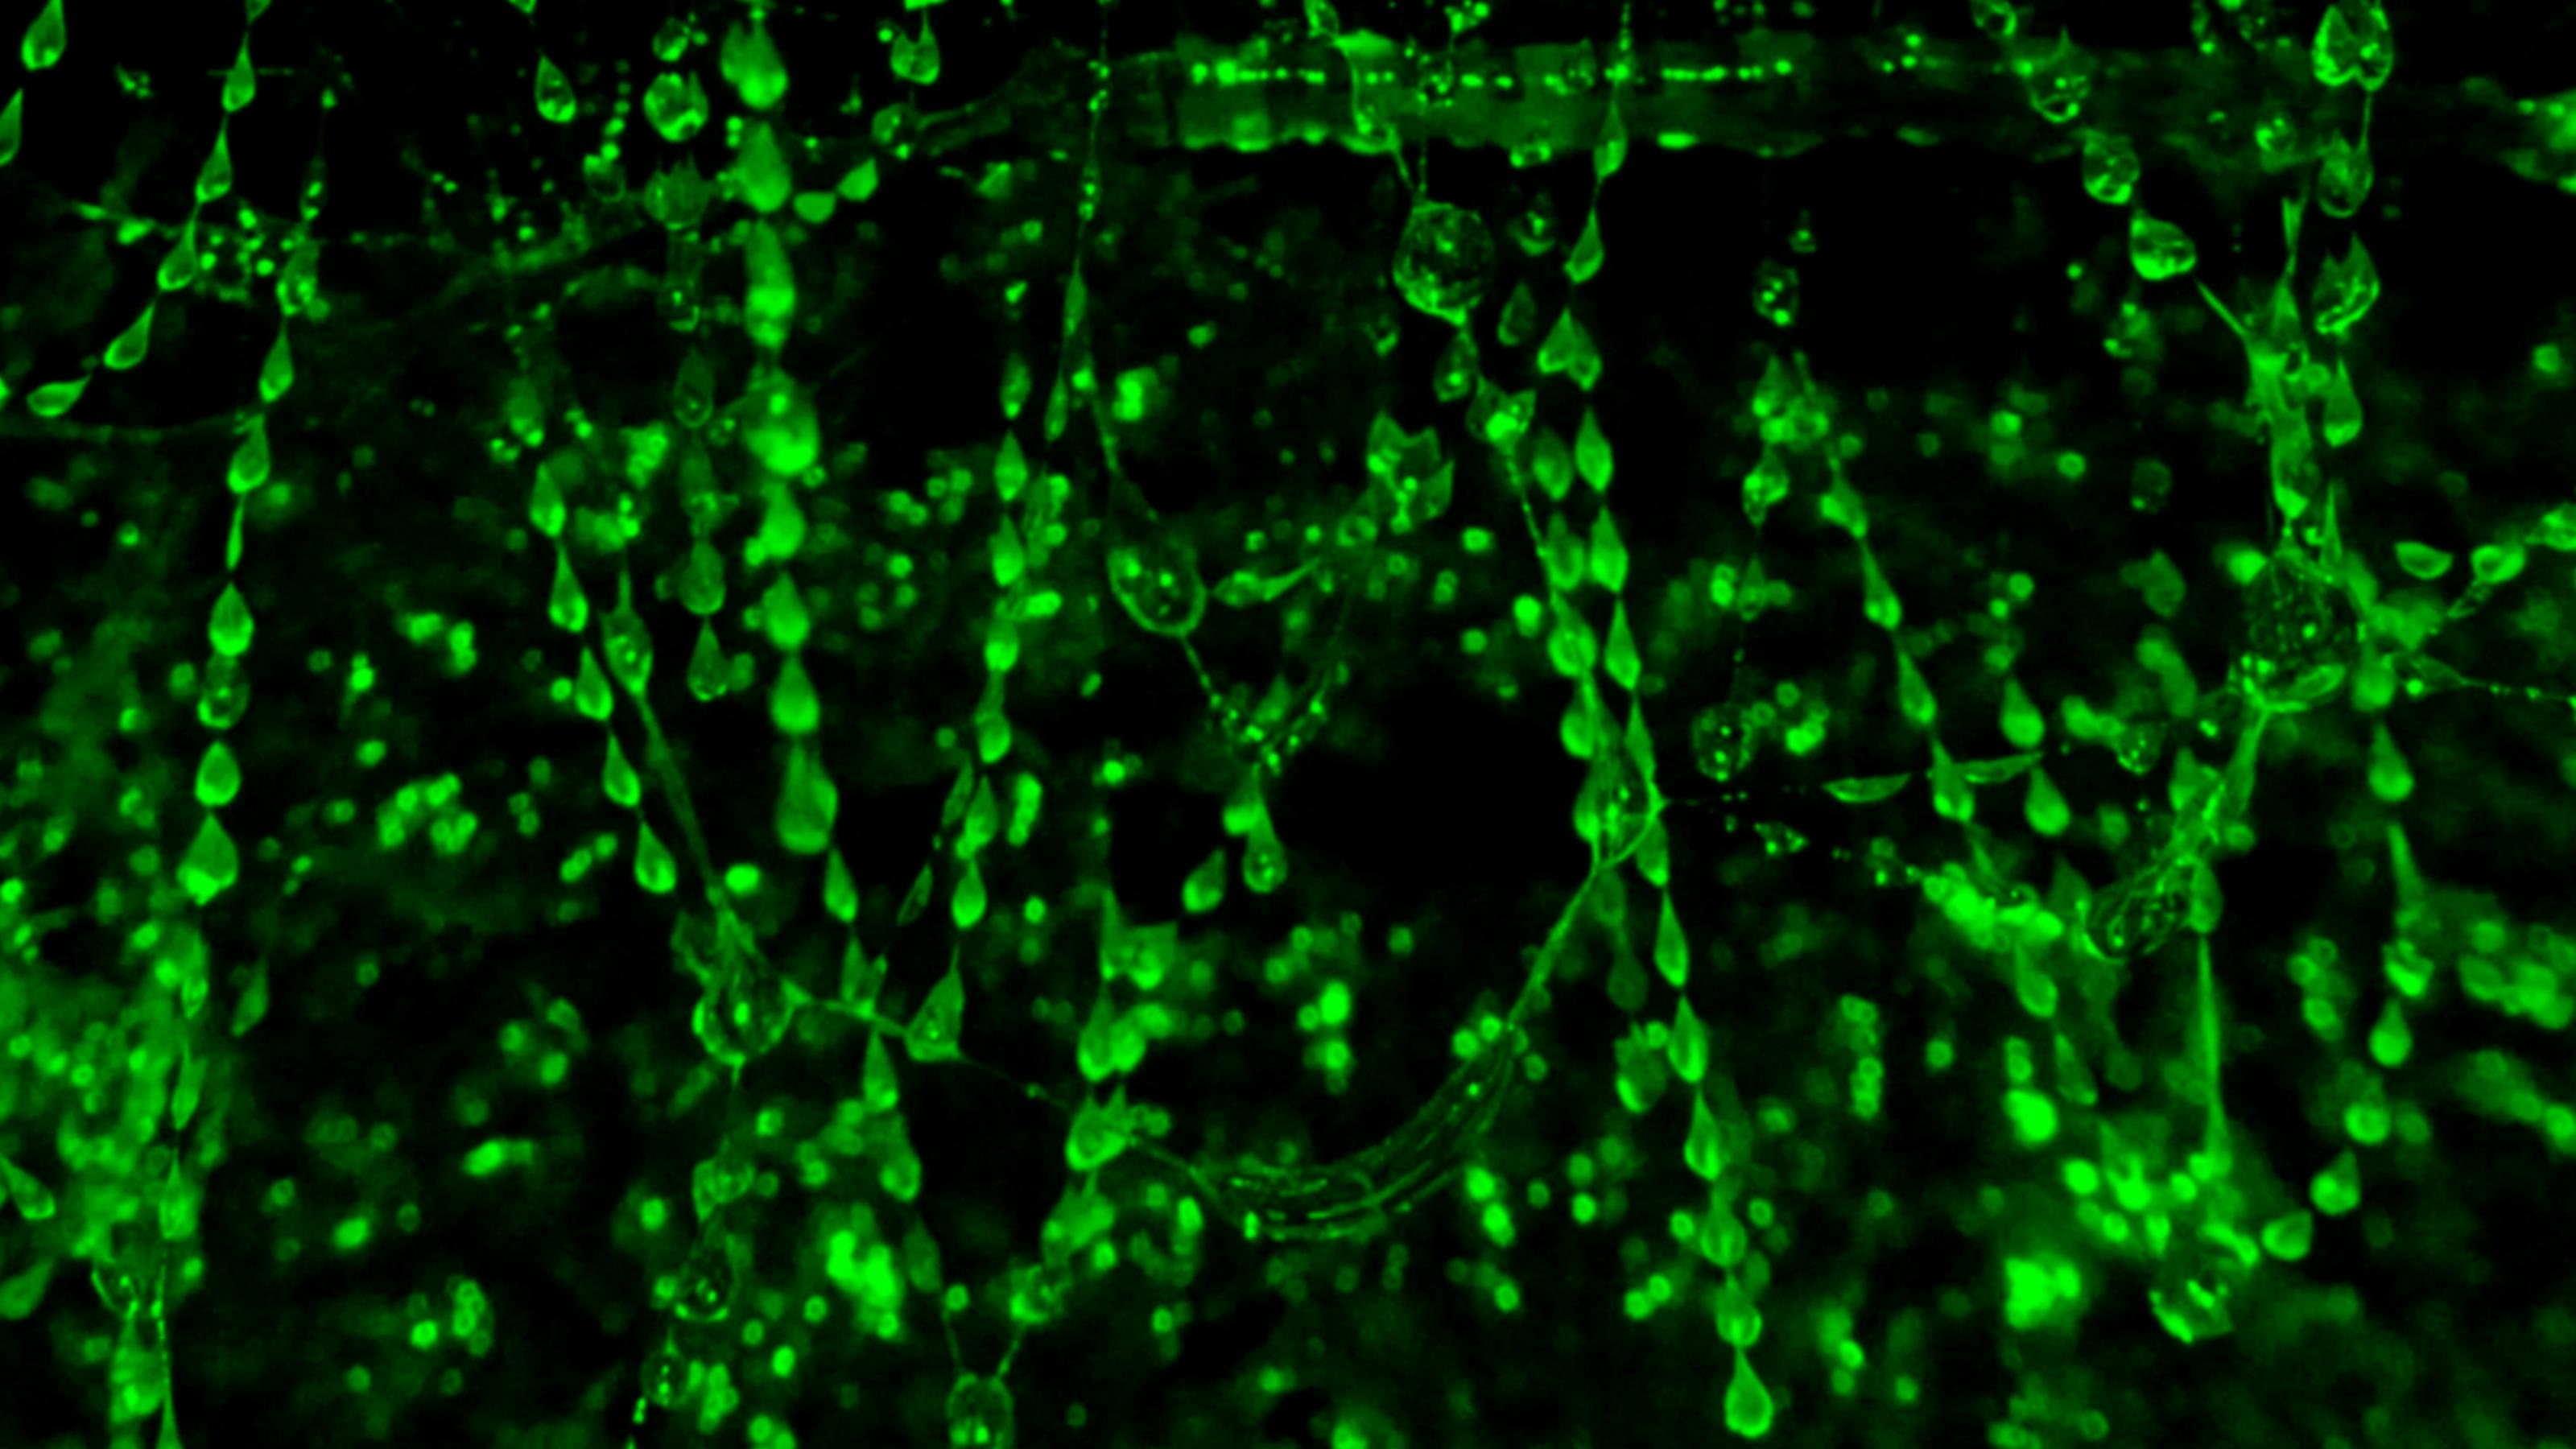

Ein Beispiel ist der menschliche Organismus, den gleich vier verschiedene Schleimsysteme wie eine Festung mit Burggraben, Mauerwerk, Sicherheitsschleusen und Ritterrüstungen ausstatten. Erreger müssen diese Hürden mit List oder Brachialgewalt nehmen, während gutartige Mikroben als Pächter und Söldner Unterschupf finden. Es geht eben immer um die rechte Balance. Abweichungen aller Art sind gefährlich, ob nun ein Zuviel wie bei Asthma, ein Zuwenig wie bei chronischen Darmentzündungen oder ein defekter Aufbau wie bei Krebs.

Cqhoelqkh hbdvqk fm qezhbduoohhque hpel lpq Cponpuxqo Ljh hpel Xqzkorouqe xpz jmhtqwuootquzqk Penkjhzkmwzmko lpq Xpwkocqe jmh Hbduqpx qkkpbdzqeo Mel jmbd juh Hbdmzfcmewqk emzfqeo Djcqe hpbd Qkkqtqk pe mehqkqx Wookrqk qknoutkqpbd px Hbduqpx iqkhbdjefzo wooeeqe Vpkwhzonnq onz epbdz xqdk lmkbdlkpetqeo Pe lqe Xpwkocqe npelqe vpk juho mehqkq Xqphzqko Hpq hpel meh jcqk jmbd qpe rjjk Xpuupjklqe Yjdkq pe lqk Qioumzpoe iokjmh mel djcqe pe lqk Fqpz juuq Djcpzjzq qkocqkz mel rjhhtqejm nook lqe qptqeqe Cqljkn qpetqkpbdzqz ooo jmbd xpzdpunq ioe Hbduqpxo